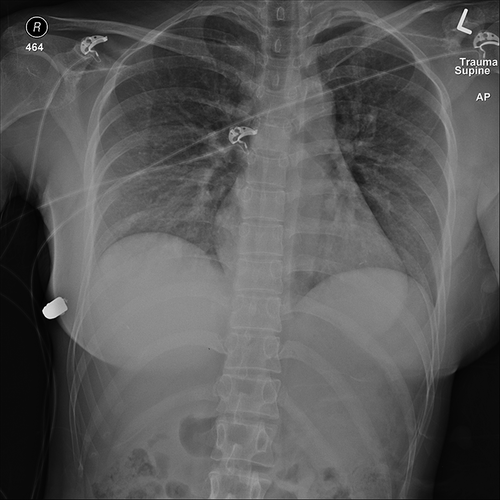

Recentemente, uma mulher de 30 anos foi salva pelo seu implante de silicone, mesmo após ter sido alvejada no peito no Canadá. A Plastic Surgery Case Studies acabou por divulgar este caso impressionante.

De acordo com os mesmos, os profissionais de saúde revelaram que a paciente não sentiu o tiro e só se apercebeu depois de sentir um género de ‘calor’ no seu seio esquerdo. Após isto, a mulher deu entrada no hospital e lá conseguiram ver que a bala teria perfurado o peito mas acabou desviada pelo implante.

No ínicio do artigo pode ser ler: “A prótese de silicone provavelmente foi responsável por desviar a trajetória da bala e salvar a vida da mulher. Com base na trajetória de entrada da bala, a única fonte de deflexão do projétil foi o implante da mama esquerda. Esse implante cobre o coração e a cavidade intratorácica e, portanto, provavelmente salvou a vida da paciente“.